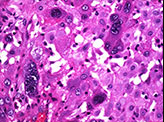

Histopathology revealed adenomyotic fragments of myometrium and hemorrhagic material, with very few degenerated villi and decidual cells{Image 3}. Multi nucleated trophoblastic cells were seen scattered in between myometrial fibres. This was suggestive of an exaggerated placental site reaction.

The immunohistochemical markers are confirmatory. The ki-67 labelling index is zero in EPS where as in placental site trophoblastic tumour , it is more than 10%. Absence of mitosis is another characteristic feature of exaggerated placental site reaction. Chorionic villi is usually present (5).